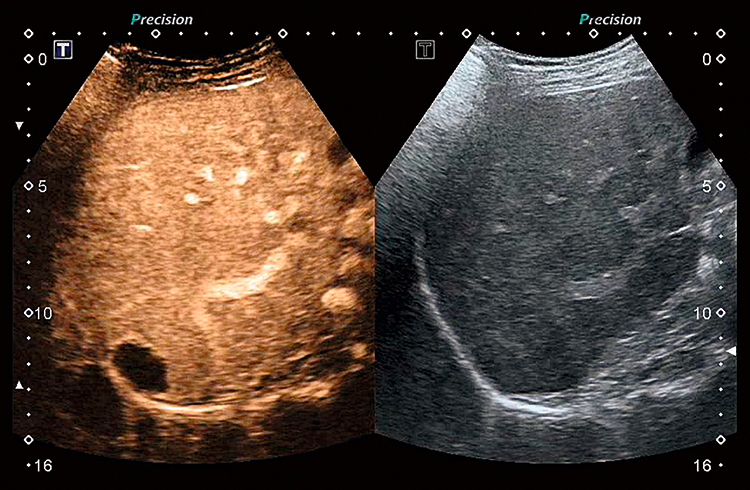

Полный пакет визуализации с контрастным усилением системы Aplio поддерживает весь спектр стандартных и специальных датчиков, позволяя оценивать динамику перфузии патологических образований, органов и тканей.

2. Продвинутые инструменты

Ультразвук с контрастным усилением (CEUS). Комплексный пакет контрастной визуализации позволяет оценить динамику перфузии в широком диапазоне клинических условий. В зависимости от конфигурации системы до 24 преобразователей поддерживают исследования с контрастным усилением, включая широкий спектр специализированных датчиков, таких как высокочастотные, интраоперационные, внутрирезонаторные и 3D / 4D преобразователи.

Контрастная количественная оценка. Набор для количественной оценки Aplio CEUS позволяет оценивать динамику перфузии с высокой точностью и гибкостью для создания объективных результатов для клинических исследований и рутинных операций. Программное обеспечение обладает высокой воспроизводимостью благодаря обработке необработанных данных и полуавтоматической функции отслеживания рентабельности инвестиций. Набор для определения контрастности доступен как опция как на консоли, так и на рабочей станции.

Полный пакет визуализации с контрастным усилением системы Aplio поддерживает весь спектр стандартных и специальных датчиков, позволяя оценивать динамику перфузии патологических образований, органов и тканей.